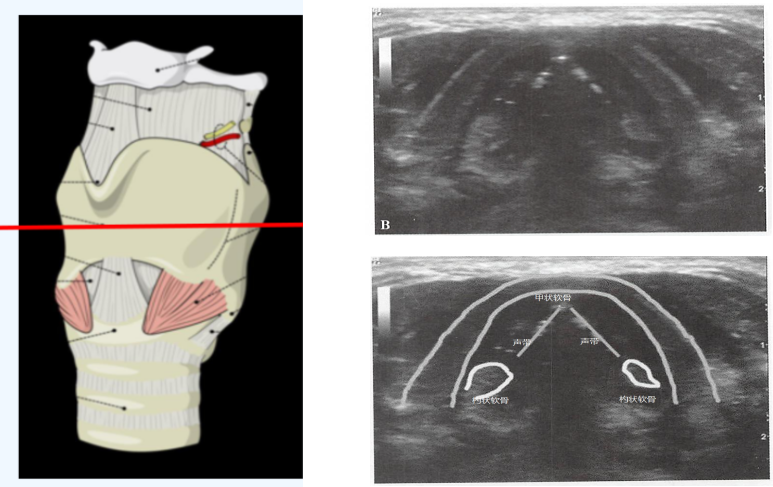

我们将高频线阵超声探头进一步下移,置于甲状软骨正前方,在没有甲状软骨钙化的个体,声带可以通过甲状软骨来呈现图6。对于钙化的个体,通过左右摇动探头30°左右来观察声带和杓状软骨。声带的声带肌表现为两三角形低回声结构,内侧为高回声的声带韧带。如果此时患者发声,可以发现两侧声带向中间运动的动态影像。

图片

图6  甲状软骨平面的扫查和声带超声结构